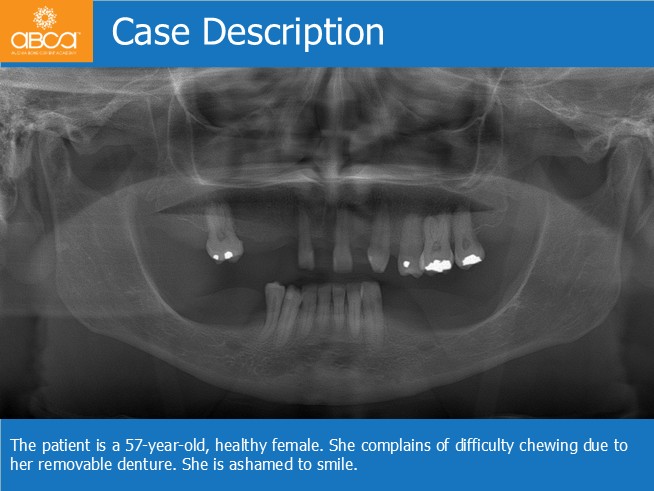

The patient is a 57-year-old, healthy female. She complains of difficulty chewing due to her removable denture. She is ashamed to smile.